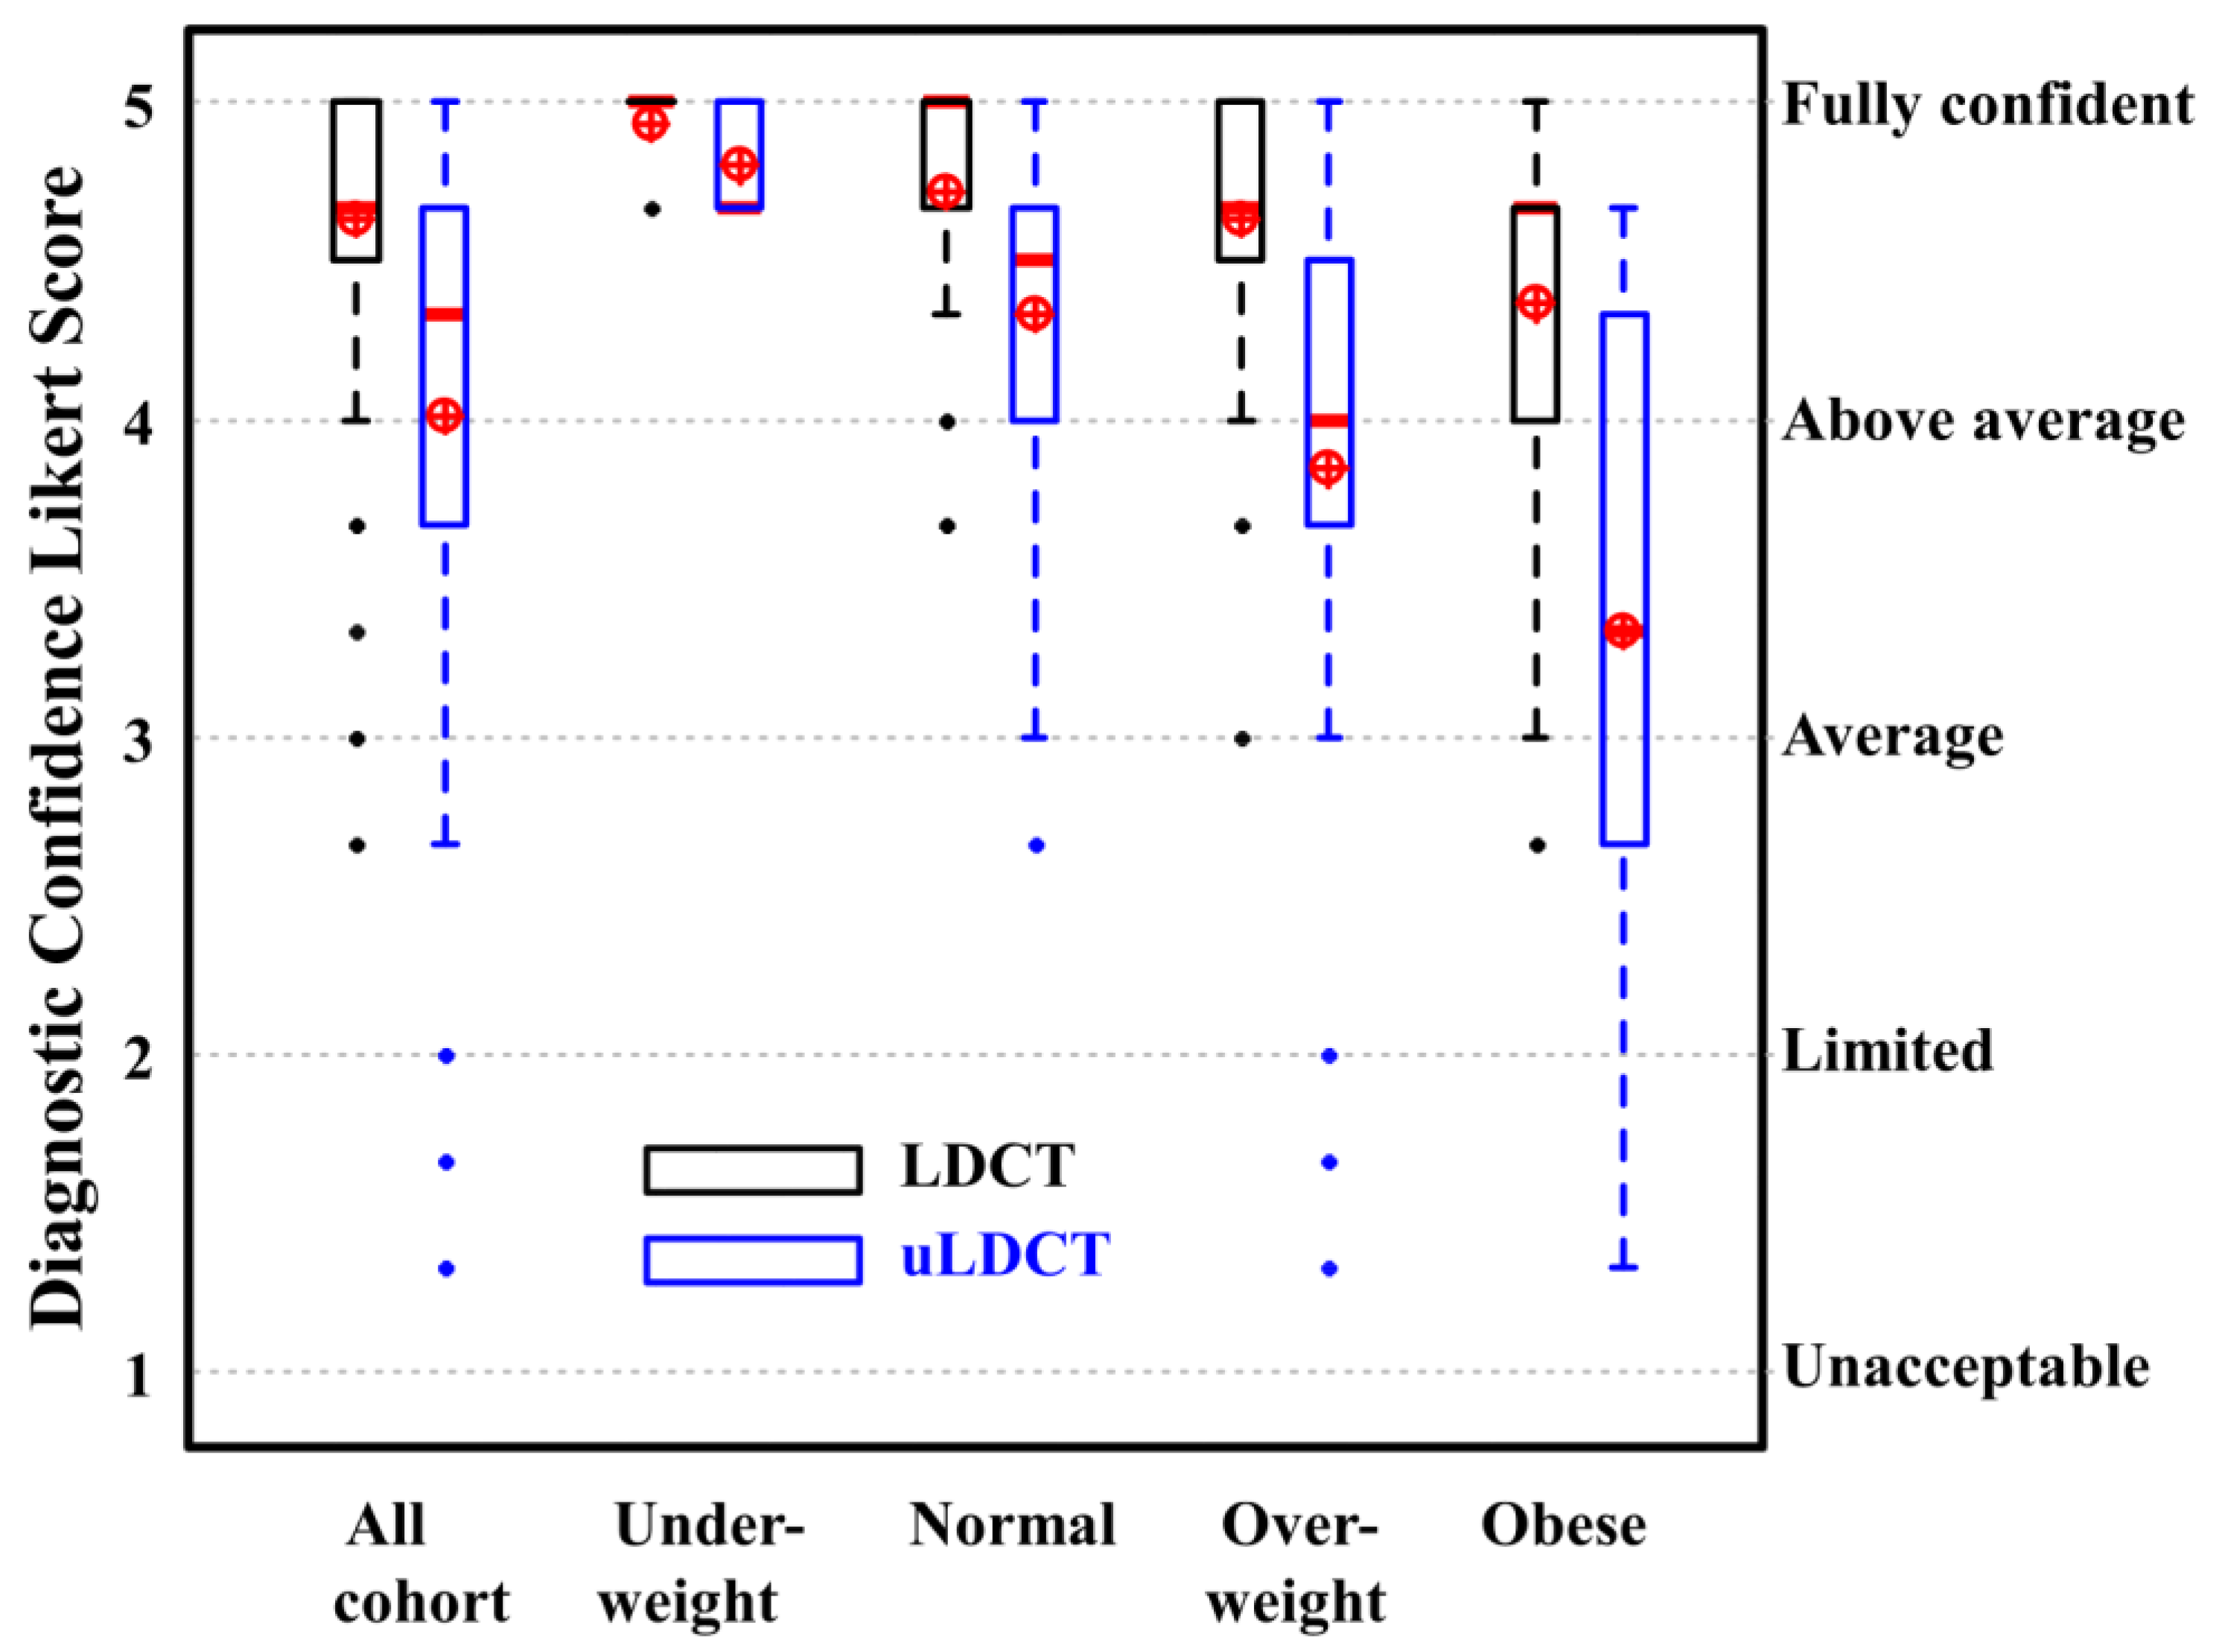

4.2. Diagnostic Confidence Assessment

5. Discussion